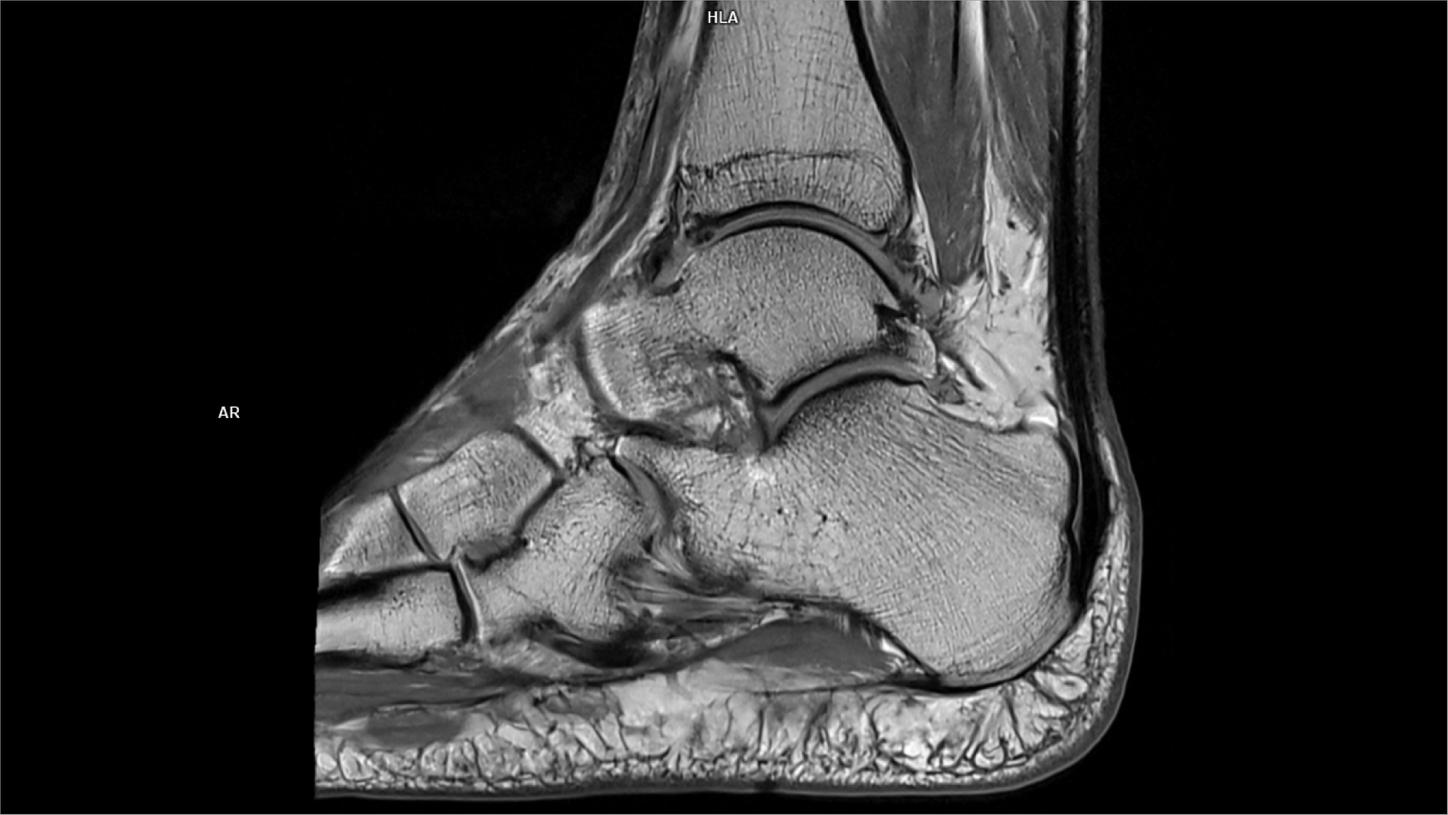

Sagittal T1 tse DR Sharp-MAGNETOM Vida

04/08/2022

Coil-Foot Ankle 16/Resolution-896/Scan Time-1:29/Aceleration-p3 DR